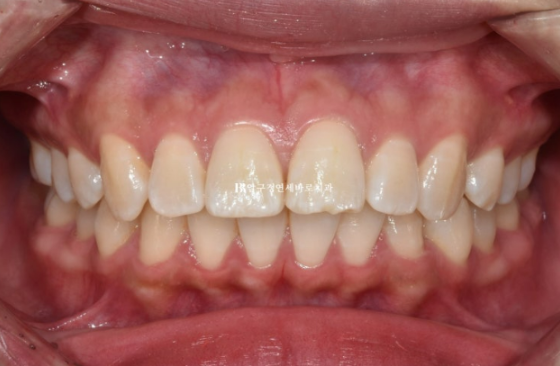

그리고 치료시작 1년 7개월째에 드디어 교정을 마치고 장치를 뗐습니다.

24.09

중심선이 맞아졌고

교합도 좋습니다.

23.02~24.09

치료기간은 총 1년 7개월입니다.

보통의 발치교정은 2년정도라고 하지만 20대 초반까지 젊은 환자분은 1년 6개월~2년 사이 정도 걸리는 것이 가장 많습니다.